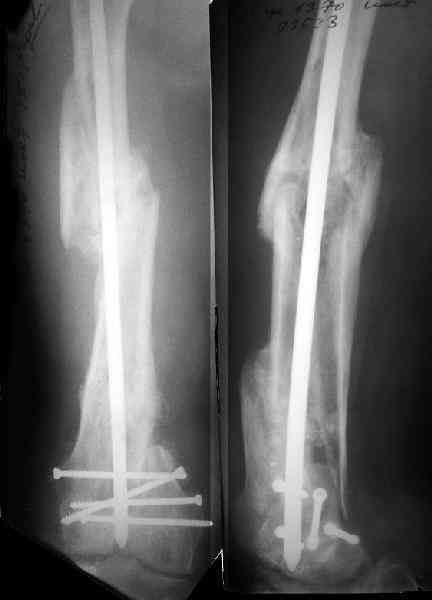

Re: Многооскольчатый перелом бедра

Это результат через полгода. К сожалению, пациент больше не приезжал на контрольный осмотр.